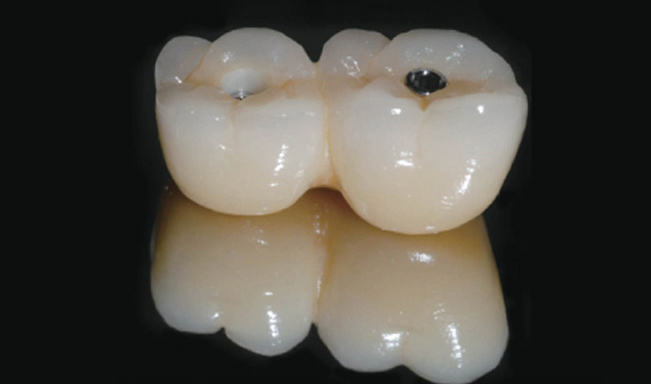

FOXDEN의 Z-plus와 X Abutment는 기존 시스템의 한계를 임상적으로 보완한 Cementless Abutment 시스템이다. 36도 이내 식립 시 별도의 각도 조절 없이 one-piece screw-retained 보철이 가능하며, 보철 단계에서의 선택지를 단순화해 준다. 실제 임상에서 수술 후 ‘이 케이스가 보철적으로 가능할지’를 다시 고민하지 않아도 된다는 점은 술자 입장에서 큰 장점으로 다가온다.

특히 스크루 홀 외벽에 경사를 부여해 보철물과 어버트먼트가 직접 접촉하도록 설계된 구조는 인상적이다. 이를 통해 교합력이 스크루에만 집중되지 않고 어버트먼트 전체로 분산되며, 보철물 장착 시 안정적인 안착감을 제공한다.

Z-plus Abutment는 Margin 두께를 충분히 확보해 밀링 과정이나 장착 후 파절 위험을 줄였고, X Abutment는 수직벽 길이를 늘려 술자의 선호와 케이스에 맞는 선택이 가능하도록 했다.